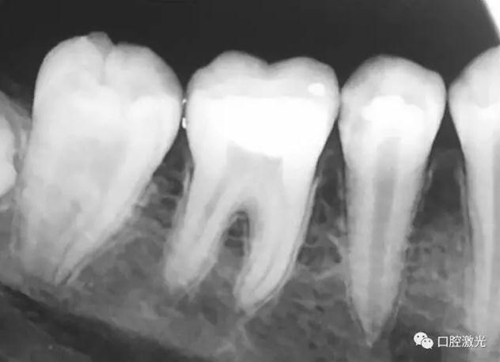

活髓理療治療結(jié)果令人滿意,沒(méi)有出血,也沒(méi)有出現(xiàn)碳化?;颊邲](méi)有感受到不適并表示滿意。為了跟蹤激光輔助活髓切除術(shù)的治療效果,手術(shù)完成即刻和5周后分別拍攝了X光圖像。5周后的牙髓活性溫度測(cè)試也顯示陽(yáng)性。

治療后即刻